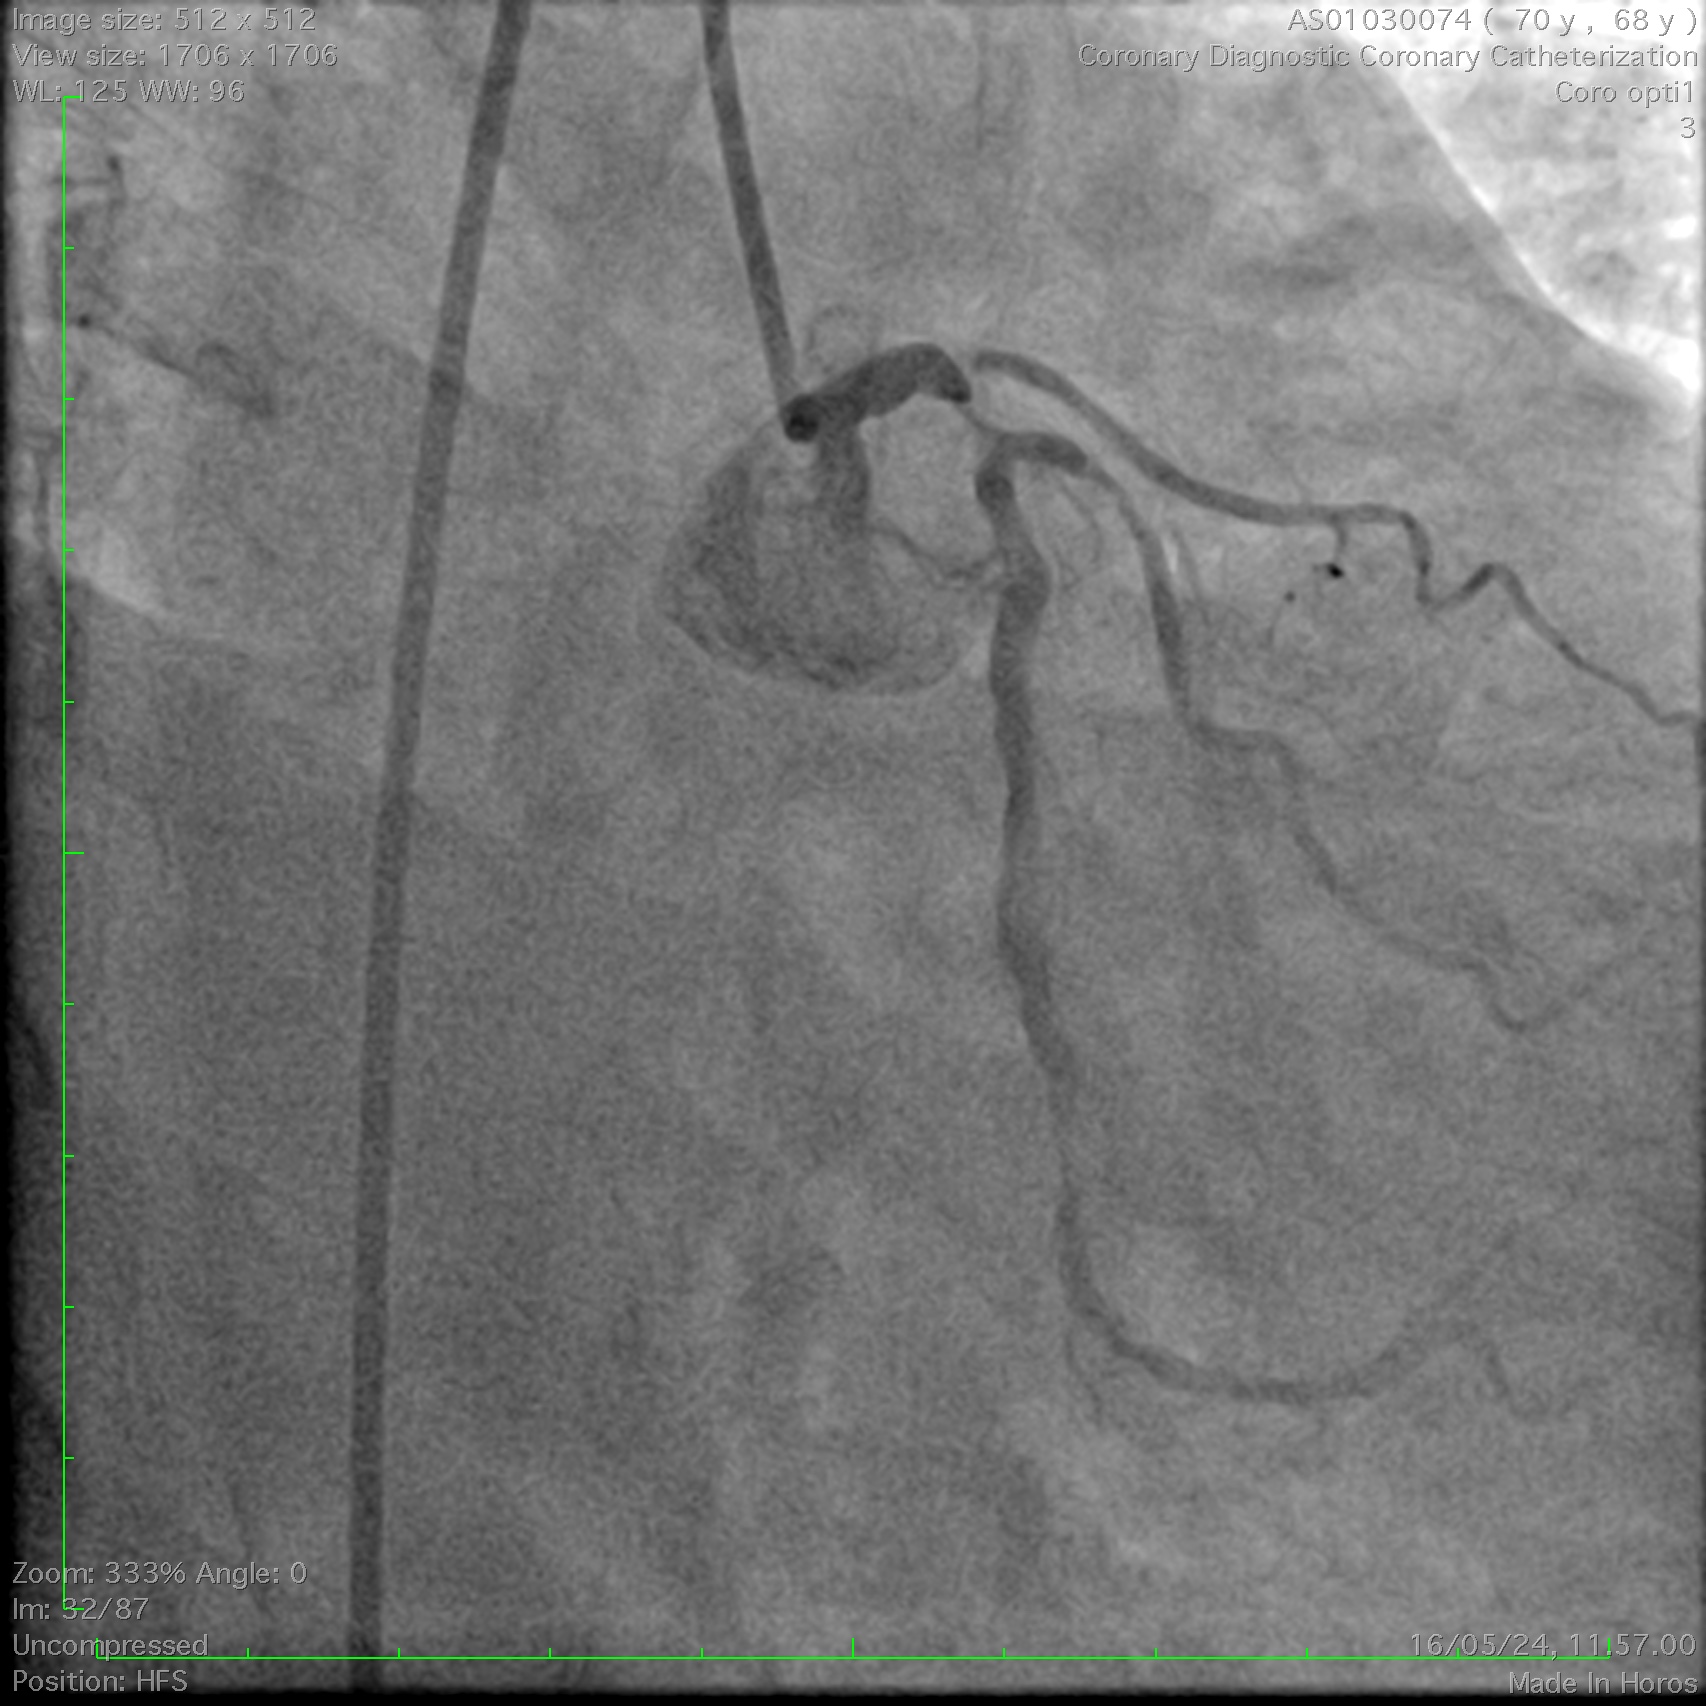

Coronary angiography demonstrated a right-dominant system with significant ostial LCx stenosis and a blunt ostial LAD chronic total occlusion, with a J-CTO score of 4. The RCA showed mild coronary disease and supplied collateral flow to the LAD territory, graded as Werner CC2.

Through bilateral femoral access, 7Fr EBU 3.5 and JR 4.0 catheters were engaged to the left main and RCA. With no antegrade entry, a retrograde marker wire and IVUS-guided antegrade puncture using Gaia Next 2 and Conquest Pro with Finecross failed, as both wires were deflected by the calcified cap despite tip modification with a secondary curve. A retrograde attempt using Gaia Next 2 and 3 with Finecross also failed.Suspecting LAD angulation, an antegrade re-attempt was performed using IVUS-guided puncture with a Conquest Pro 8-20 supported by a Supercross90 under retrograde wire guidance, successfully puncturing the proximal cap. Supercross was exchanged for Finecross, and the wire crossed distally, but Finecross and Corsair Pro XS could not advance due to the tight lesion. After proximal preparation and the anchor balloon technique in the LCx, the microcatheter advanced distally and the wire was exchanged for a workhorse wire. Retrograde injections confirmed true lumen position, and the LAD was predilated. IVUS showed mixed plaque and myocardial bridging in the mid LAD and mixed plaque at the ostial LCx. Further preparation was performed with a 3.5 mm scoring balloon. A hybrid strategy using a 4.0¡¿20 mm DCB for the LCx and a 4.0¡¿32 mm DES from LM to LAD, followed by 5.0 and 4.0 NC balloons for post-dilatation, achieved final TIMI 3 flow without complications.